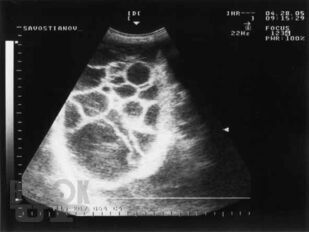

Материалом послужили данные многолетнего обследования больных декомпенсированным циррозом печени, проанализированы клинические проявления спонтанного бактериального перитонита, в том числе системной воспалительной реакции, использован широкий комплекс современных методов: подсчет полиморфноядерных нейтрофилов в асцитической жидкости, микробиологическое исследование крови и асцита, ультразвуковая оценка акустической однородности асцита, исследовано содержание цитокинов, С-реактивного белка, количественный и качественный состав химических компонентов – маркеров потенциальных возбудителей инфекции асцитической жидкости методом газовой хроматографии-масс-спектрометрии. В работе представлены результаты исследования позволяющие диагностировать спонтанный бактериальный перитонит на более ранних сроках, что позволяет проводить своевременную адекватную терапию. Рассмотрены вопросы дифференциальной диагностики первичного и вторичного бактериального перитонита, приведены яркие клинические примеры, отражающие трудности диагностики.

В книге на основе анализа литературы и собственных данных автором представлены современные аспекты этиологии, патогенеза, диагностики, профилактики и лечения спонтанного бактериального перитонита у больных циррозом печени. Материалом послужили данные многолетнего обследования больных декомпенсированным циррозом печени, проанализированы клинические проявления спонтанного бактериального перитонита, в том числе системной воспалительной реакции, использован широкий комплекс современных методов: подсчет полиморфноядерных нейтрофилов в асцитической жидкости, микробиологическое исследование крови и асцита, ультразвуковая оценка акустической однородности асцита, исследовано содержание цитокинов, С-реактивного белка, количественный и качественный состав химических компонентов – маркеров потенциальных возбудителей инфекции асцитической жидкости методом газовой хроматографии-масс-спектрометрии.